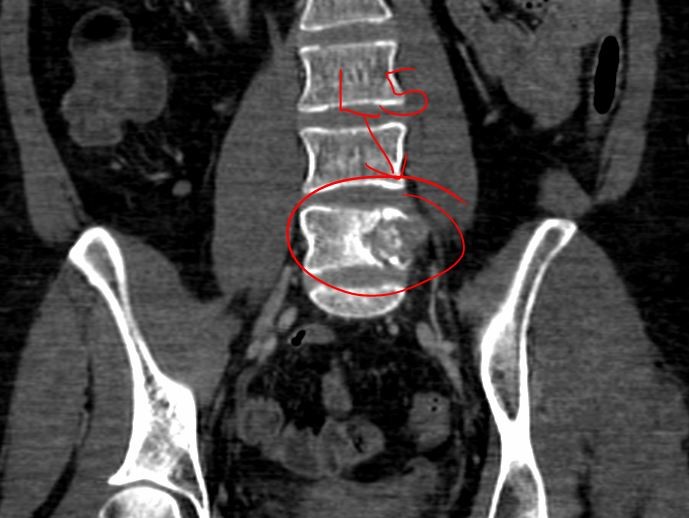

Dos años después, a tres meses de haber finalizado sus

bloqueos, nuevamente en el mes de octubre del presente año, un

nuevo diagnóstico determina que el tratamiento anterior falló y

ahora debe enfrentar que el diagnóstico inicial se ha extendido a 1

vértebra de su columna vertebral y a 2 ganglios más del lado derecho

de la mama afectada.